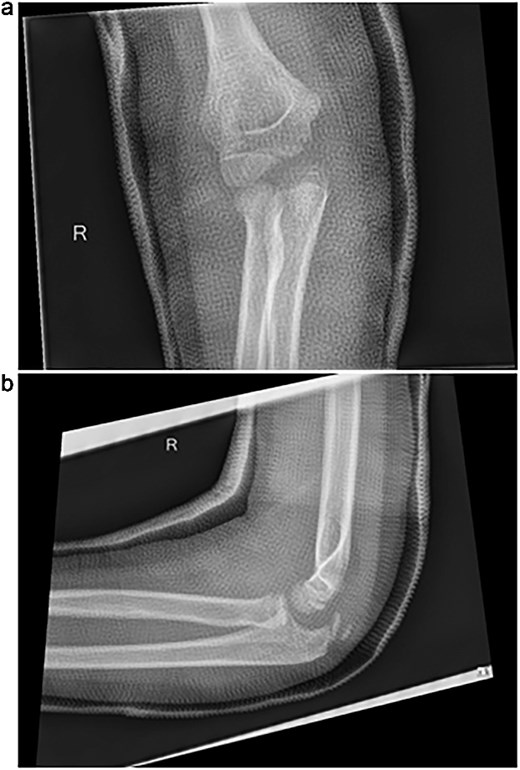

Initial radiographs following closed reduction and casting demonstrated fractures of the proximal ulna and radial neck, with improved alignment but limited bony detail (Fig. 1a and b). Elbow effusion was also noted. A CT scan performed 3 days later showed 18° apex-medial angulation of the radial neck fracture, slight inferior subluxation of the radial head, and linear calcification near the ulnotrochlear interval, concerning for an intra-articular fragment (Fig. 2).

(a, b) Initial radiographs after closed reduction, showing proximal ulna and radial neck fractures.